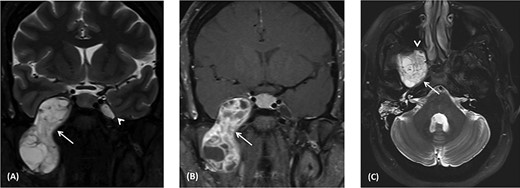

(A) Coronal CT image using bone window shows remodeling and widening of the oval foramen (arrow) secondary to infratemporal/middle cranial fossa mass. (B) axial CT images using bone window at the level of oval window demonstrates the widening of the canal with extension medially resulting in dehiscence of the anterior wall of the carotid canal (arrow). (C) Axial CT image using bone window at the infratemporal fossa level shows erosion and remodeling of the right pterygoid plates (Arrow) as well as the right mandible (arrowhead).

Computed tomography (CT) scan shows remodeling and widening of the right foramen ovale (Fig. 2A). This is associated with focal dehiscence at the right lateral wall of the sphenoid sinus and the anterior wall of the right carotid canal (Fig. 2B). The lesion extends downwards to the infratemporal fossa with remodeling of the pterygoid plates (Fig. 2C) and the right mandibular ramus.